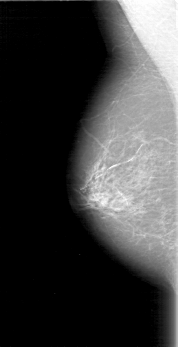

D_4097_1.RIGHT_CC

RIGHT_CC LINES 4606 PIXELS_PER_LINE 2056 BITS_PER_PIXEL 12 RESOLUTION 43.5 NON_OVERLAY

RIGHT_MLO LINES 5191 PIXELS_PER_LINE 2656 BITS_PER_PIXEL 12 RESOLUTION 43.5 NON_OVERLAY